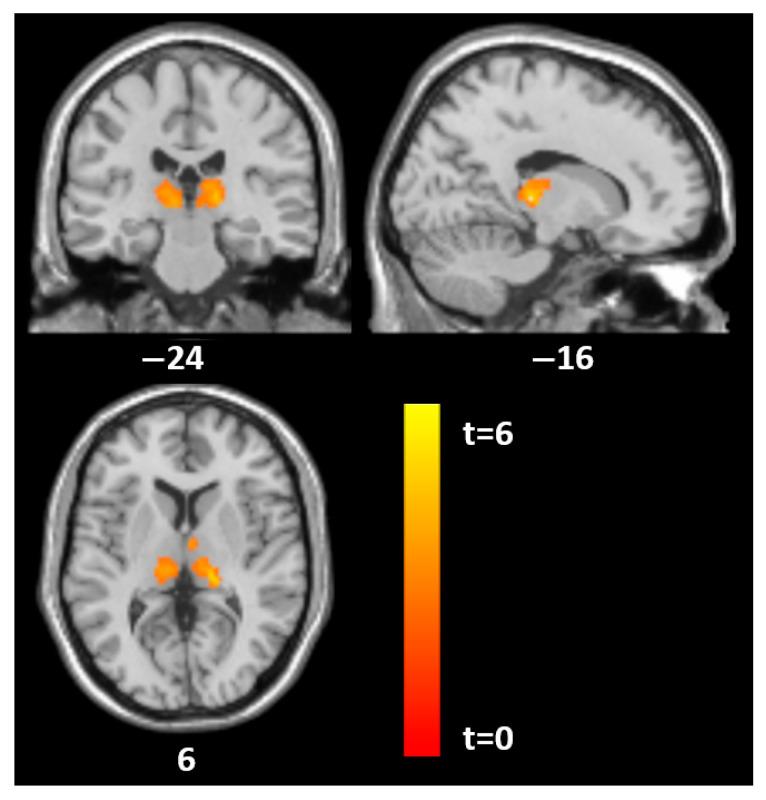

: Comorbid personality disorders (PDs) in patients with anorexia nervosa (AN) are associated with increased psychopathology, higher suicide risk, and poorer treatment response and outcomes. This study aimed to examine associations between gray matter (GM) volume and PDs in female adolescents with AN before and after short-term psychotherapeutic and nutritional therapy. : Eighteen female adolescents with acute AN, mean age 15.9 years, underwent 3T magnetic resonance imaging before and after weight restoration. The average interval between scans was 2.6 months. Structural brain changes were analyzed using voxel-based morphometry. PDs were assessed using the Structured Clinical Interview for DSM-IV Axis II Disorders (SCID II) and the Assessment of Identity Development Questionnaire. : SCID-II total scores showed significant positive associations with GM volume in the mid-cingulate cortex at both time points and in the left superior parietal-occipital lobule at baseline. The histrionic subscale correlated with GM volume in the thalamus bilaterally and the left superior parietal-occipital lobule in both assessments, as well as with the mid-cingulate cortex at follow-up. Borderline and antisocial subscales were associated with GM volume in the thalamus bilaterally at baseline and in the right mid-cingulate cortex at follow-up. : PDs in female adolescent patients with AN may be specifically related to GM alterations in the thalamus, cingulate, and parieto-occipital regions, which are present during acute illness and persist after weight restoration therapy.

神经性厌食症(AN)患者的共病性人格障碍(PDs)与精神病理学增加、自杀风险升高以及治疗反应和结果较差有关。本研究旨在探讨短期心理治疗和营养治疗前后,患有AN的女性青少年的灰质(GM)体积与PDs之间的关联。18名患有急性AN的女性青少年,平均年龄15.9岁,在体重恢复前后接受了3T磁共振成像检查。两次扫描的平均间隔时间为2.6个月。使用基于体素的形态计量学分析大脑结构变化。使用《精神疾病诊断与统计手册》第四版轴II障碍的结构化临床访谈(SCID II)和身份发展评估问卷对PDs进行评估。SCID-II总分在两个时间点均与扣带回中部的GM体积以及基线时左侧顶上枕叶的GM体积呈显著正相关。在两次评估中,表演型分量表均与双侧丘脑以及左侧顶上枕叶的GM体积相关,并且在随访时与扣带回中部相关。边缘型和反社会型分量表在基线时与双侧丘脑的GM体积相关,在随访时与右侧扣带回中部的GM体积相关。患有AN的女性青少年患者的PDs可能与丘脑、扣带回和顶枕叶区域的GM改变特别相关,这些改变在急性疾病期间存在,并在体重恢复治疗后持续存在。